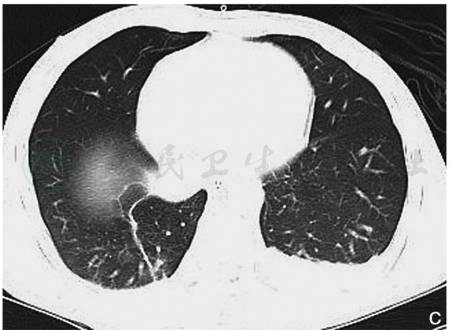

图7双肺复合性挫裂伤

男性,56岁,胸部CT平扫肺窗(A、B)显示双肺膨胀不良,双肺野内见片状及絮状高密度影,边界模糊;双肺内另见囊状透亮影(实箭),胸壁、胸腔、纵隔内见气体密度影(虚箭),纵隔窗(C、D)显示双侧胸腔积液

引自:中华影像医学·呼吸系统卷.第3版.ISBN:978-7-117-28903-0.主编:

图8肺血肿及肺气囊

男性,23岁,胸部CT平扫肺窗(A)显示左肺下叶团块状高密度影(实箭),周围见挫伤肺组织,同时可见外伤性肺气囊(虚箭);同层纵隔窗(B)显示左肺下叶软组织及稍高密度影